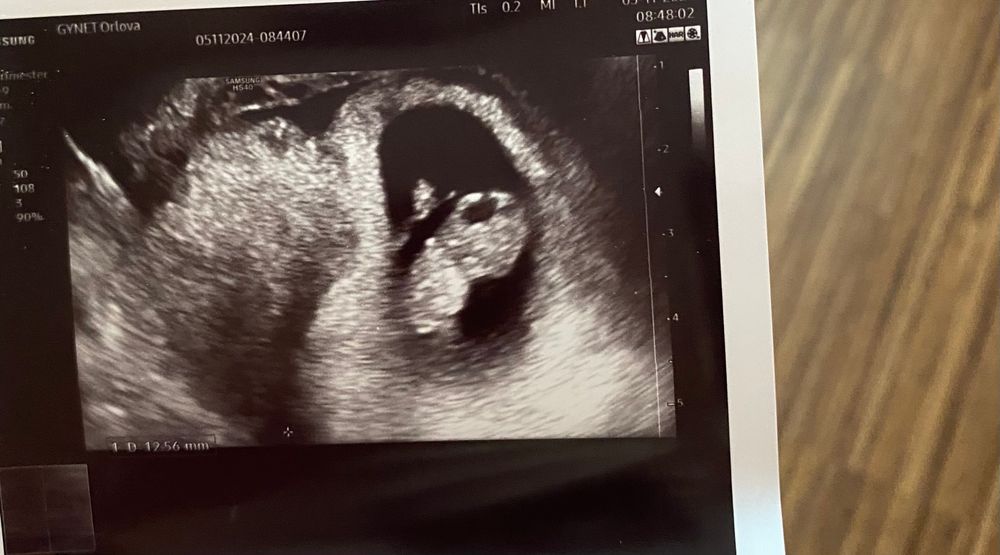

Девочки , подскажите на сколько опасна така гематома 9 недель беременности , врач сказала принимать вагинальное прогестерон, но читала что такая гематома очень опасная, теперь волнуюсь